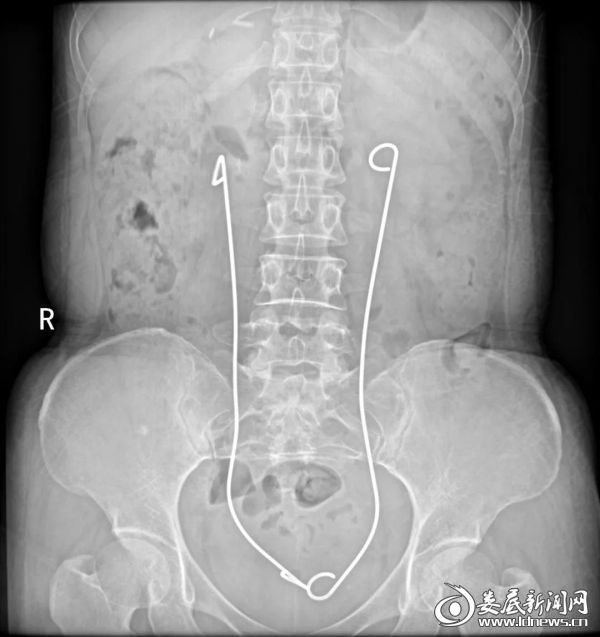

娄底新闻网讯(通讯员 刘嘉 邹珍琪)邓女士是一位宫颈癌晚期肿瘤转移至输尿管的患者,输尿管梗阻导致双肾积水,肾功能损害,曾在上海知名医院放置输尿管支架失败。辗转来到娄星区人民医院(娄星区妇幼保健院)泌尿外科住院治疗,检查发现双肾中重度积水,肾功能损害严重,进一步发展有引起肾功能衰竭、尿毒症的可能。科室主任王卫东在详细询问病史、查体及阅读检察结果后,考虑到患者的特殊性及在外院放置传统输尿管支架失败这一情况,针对手术风险、并发症及预后等情况充分评估,制定了科学、周密的手术方案,建议可在科室首创的B超实时监控下行输尿管镜金属支架留置术治疗。

取得患者及家属同意后,王卫东携手术团队成功完成了湘中地区第一例输尿管金属支架留置术,手术顺利,症状明显缓解,术后恢复良好。

据了解,复杂性的输尿管狭窄,如长段输尿管狭窄,直肠癌,宫颈癌等恶性肿瘤晚期压迫输尿管而导致的输尿管梗阻,目前,有腹壁输尿管皮肤造口术,经皮肾穿刺造瘘术,膀胱壁输尿管吻合成形等方法,上述操作,难度大,出血等并发症多见,降低了患者的生命质量,而放置传统的输尿管支架为硅胶树脂,聚氨酯材质制成,质地较软,管腔较细,抗外压能力有限,容易堵塞,且不能在体内长期留置,部分患者后期更换输尿管支架难度大,失败率高,操作过程中容易引起出血,尿路感染等并发症。且反复更换支架管,增加了患者的医疗花费及身体的损害,与传统的聚合物支架相比,金属支架虽然首次治疗费用较高,换管的频率却可以减少为一年一次,而传统输尿管支架每年换管频率为3~6次,因此金属支架较传统输尿管支架性价比更高,对于改善复杂性输尿管狭窄患者的生存质量,有很好的帮助。